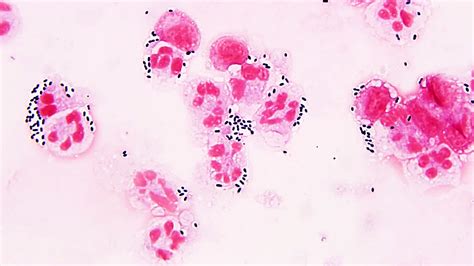

Alright, let’s get down to the nitty-gritty of Streptococcus bacteria . These guys are Gram-positive, which basically means when you look at them under a microscope after a special staining process, they show up a certain color and have a specific type of cell wall. They’re also cocci, meaning they’re spherical or oval-shaped. What’s super distinctive about them is how they arrange themselves – they typically form chains or pairs, kind of like little beads on a string, which is where the name ‘Streptococcus’ comes from (from the Greek word ‘streptos’ meaning twisted or chain-like). This arrangement is a big clue for microbiologists when they’re trying to identify them. But don’t let their simple shape fool you; these bacteria are incredibly diverse. They can be found all over the place – on our skin, in our mouths, and in our digestive tracts – and many of them are actually harmless, even beneficial, part of our natural flora. They’re like tiny tenants living on and in us! However, some strains are opportunistic pathogens, meaning they can cause trouble when the conditions are right, like if our immune system is weakened or if they find their way into parts of the body where they shouldn’t be. This duality is what makes studying Streptococcus so interesting and crucial for public health. The sheer variety within the Streptococcus genus means that not all strains are created equal when it comes to causing disease. Some are incredibly virulent, meaning they can cause severe illness quickly, while others are much more benign. Scientists classify these bacteria using different methods, including how they look under the microscope, their biochemical properties, and importantly, their hemolytic activity – that is, whether and how they break down red blood cells in a lab setting. This classification system helps doctors and researchers distinguish between the different types and predict their potential impact on human health.